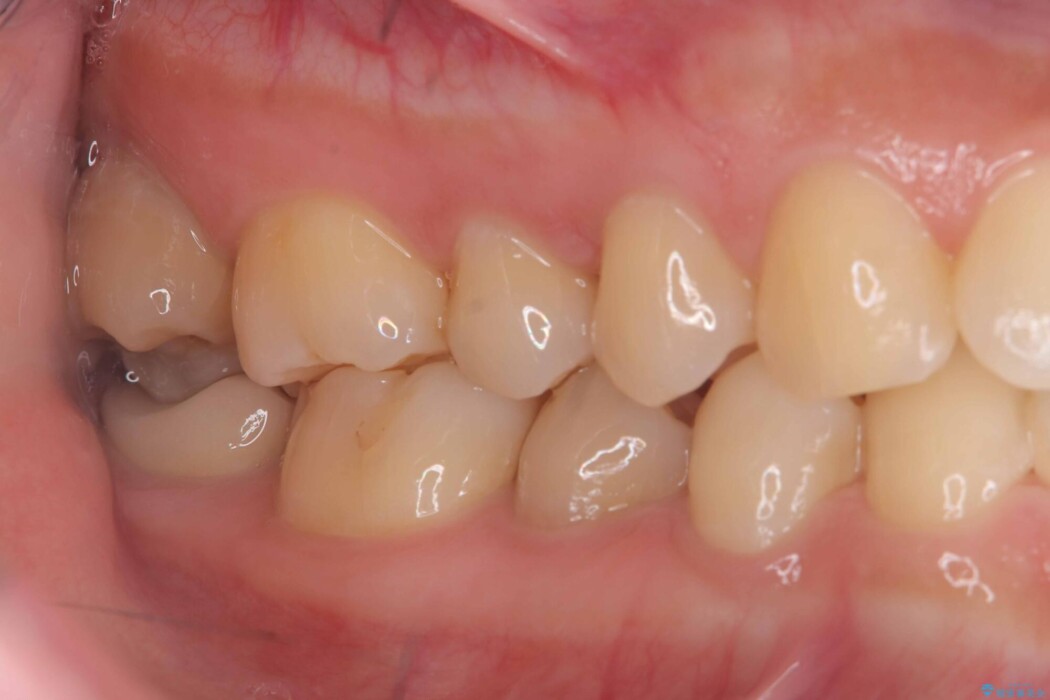

クラウンにすることで、歯全体を保護しながら、見た目も自然で長期的に安定した状態を維持しやすくなります。

「できるだけ歯を削りたくない」という考えも大切ですが、状態によっては、長持ちさせるためにあえて全体を覆う治療が適している場合もあります。